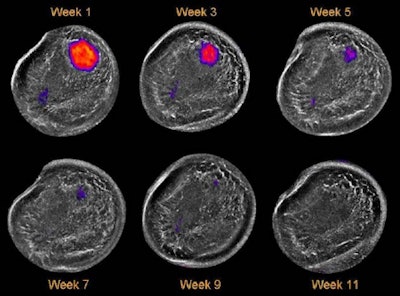

![]() |

As chemotherapy takes effect over time, the tumor shrinks in size and falls below the pixel visualization threshold.

"More importantly, as far as we're concerned, is that we're also seeing an effect where the average sound speed of the breast is also declining," he said. "And we see this as a somewhat independent marker of the size of the tumor, because what it's telling us is that the tumor is getting softer and softer."

In further analysis of their sample of 11 neoadjuvant chemotherapy monitoring patients, the researchers found a significant difference between patients who responded fully to chemotherapy and those who had a partial response. The average starting sound speed of the responders was lower and the rate of tumor decline was much steeper than for the partial responders, he said.